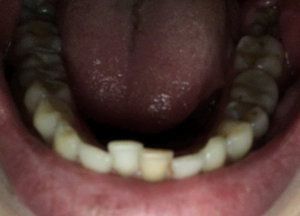

Что можно сделать, чтобы выровнять зубы? Сначала нужно поставить пластину, а потом уже брекеты?

• Пластинка наиболее эффективна в детском возрасте, в период молочных зубов. После прорезывания постоянных зубов показано лечение на брекет-системе. А пластинка в период постоянного прикуса малоэффективна. По фотографии сложно определить Ваш возраст, но судя по фотографии зубы уже постоянные. Поэтому можно начинать сразу с брекетов.